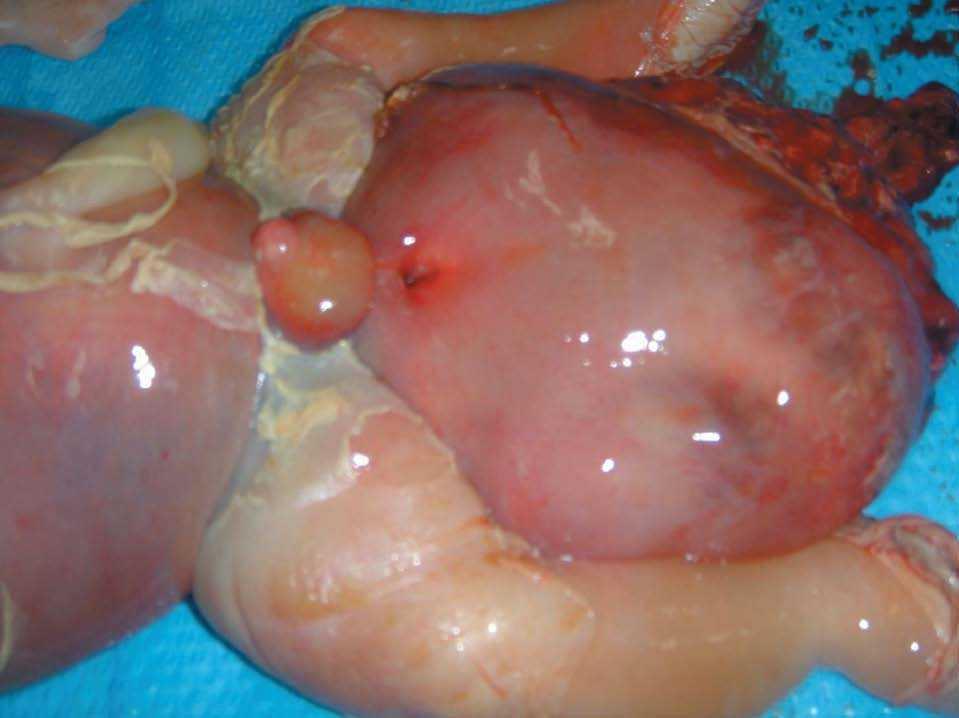

Se repitió la ecografía a los 2 días (semana 28 + 2), donde se puso de manifiesto la presentación cefálica del feto, con ausencia de frecuencia cardíaca y otros signos de muerte fetal intraútero. El perímetro de la tumoración era de 353 mm, bastante superior al perímetro abdominal, de unos 290 mm.

Tras el diagnóstico de muerte fetal intraútero, se decidió el ingreso de la madre para finalizar la gestación. Considerando los antecedentes de la gestante, y tras constatar unas condiciones cervicales no del todo desfavorables (Bishop de 3), se decidió la inducción del parto. Se alcanzó una dilatación completa en 8 h y se produjo la expulsión de feto en cefálica, con salida de la masa descrita sin dificultad. Microscópicamente, era evidente el edema generalizado en toda la anatomía fetal, destacando un desplazamiento de los miembros inferiores por la gran tumoración, y unos genitales masculinos muy edematizados; la masa medía unos 13 cm de diámetro, de componente sólido fundamentalmente (figs. 9-12).

Figura 9.Feto tras el parto vaginal: edemas generalizados en toda la superficie corporal. Masa heterogénea de gran tamaño que corresponde a un teratoma sacrococcígeo.

Figura 10.Detalle de la masa, que mide unos 13 cm, con tejido heterogéneo.

Figura 11.Edemas importantes en los miembros inferiores que distorsionan los genitales externos.